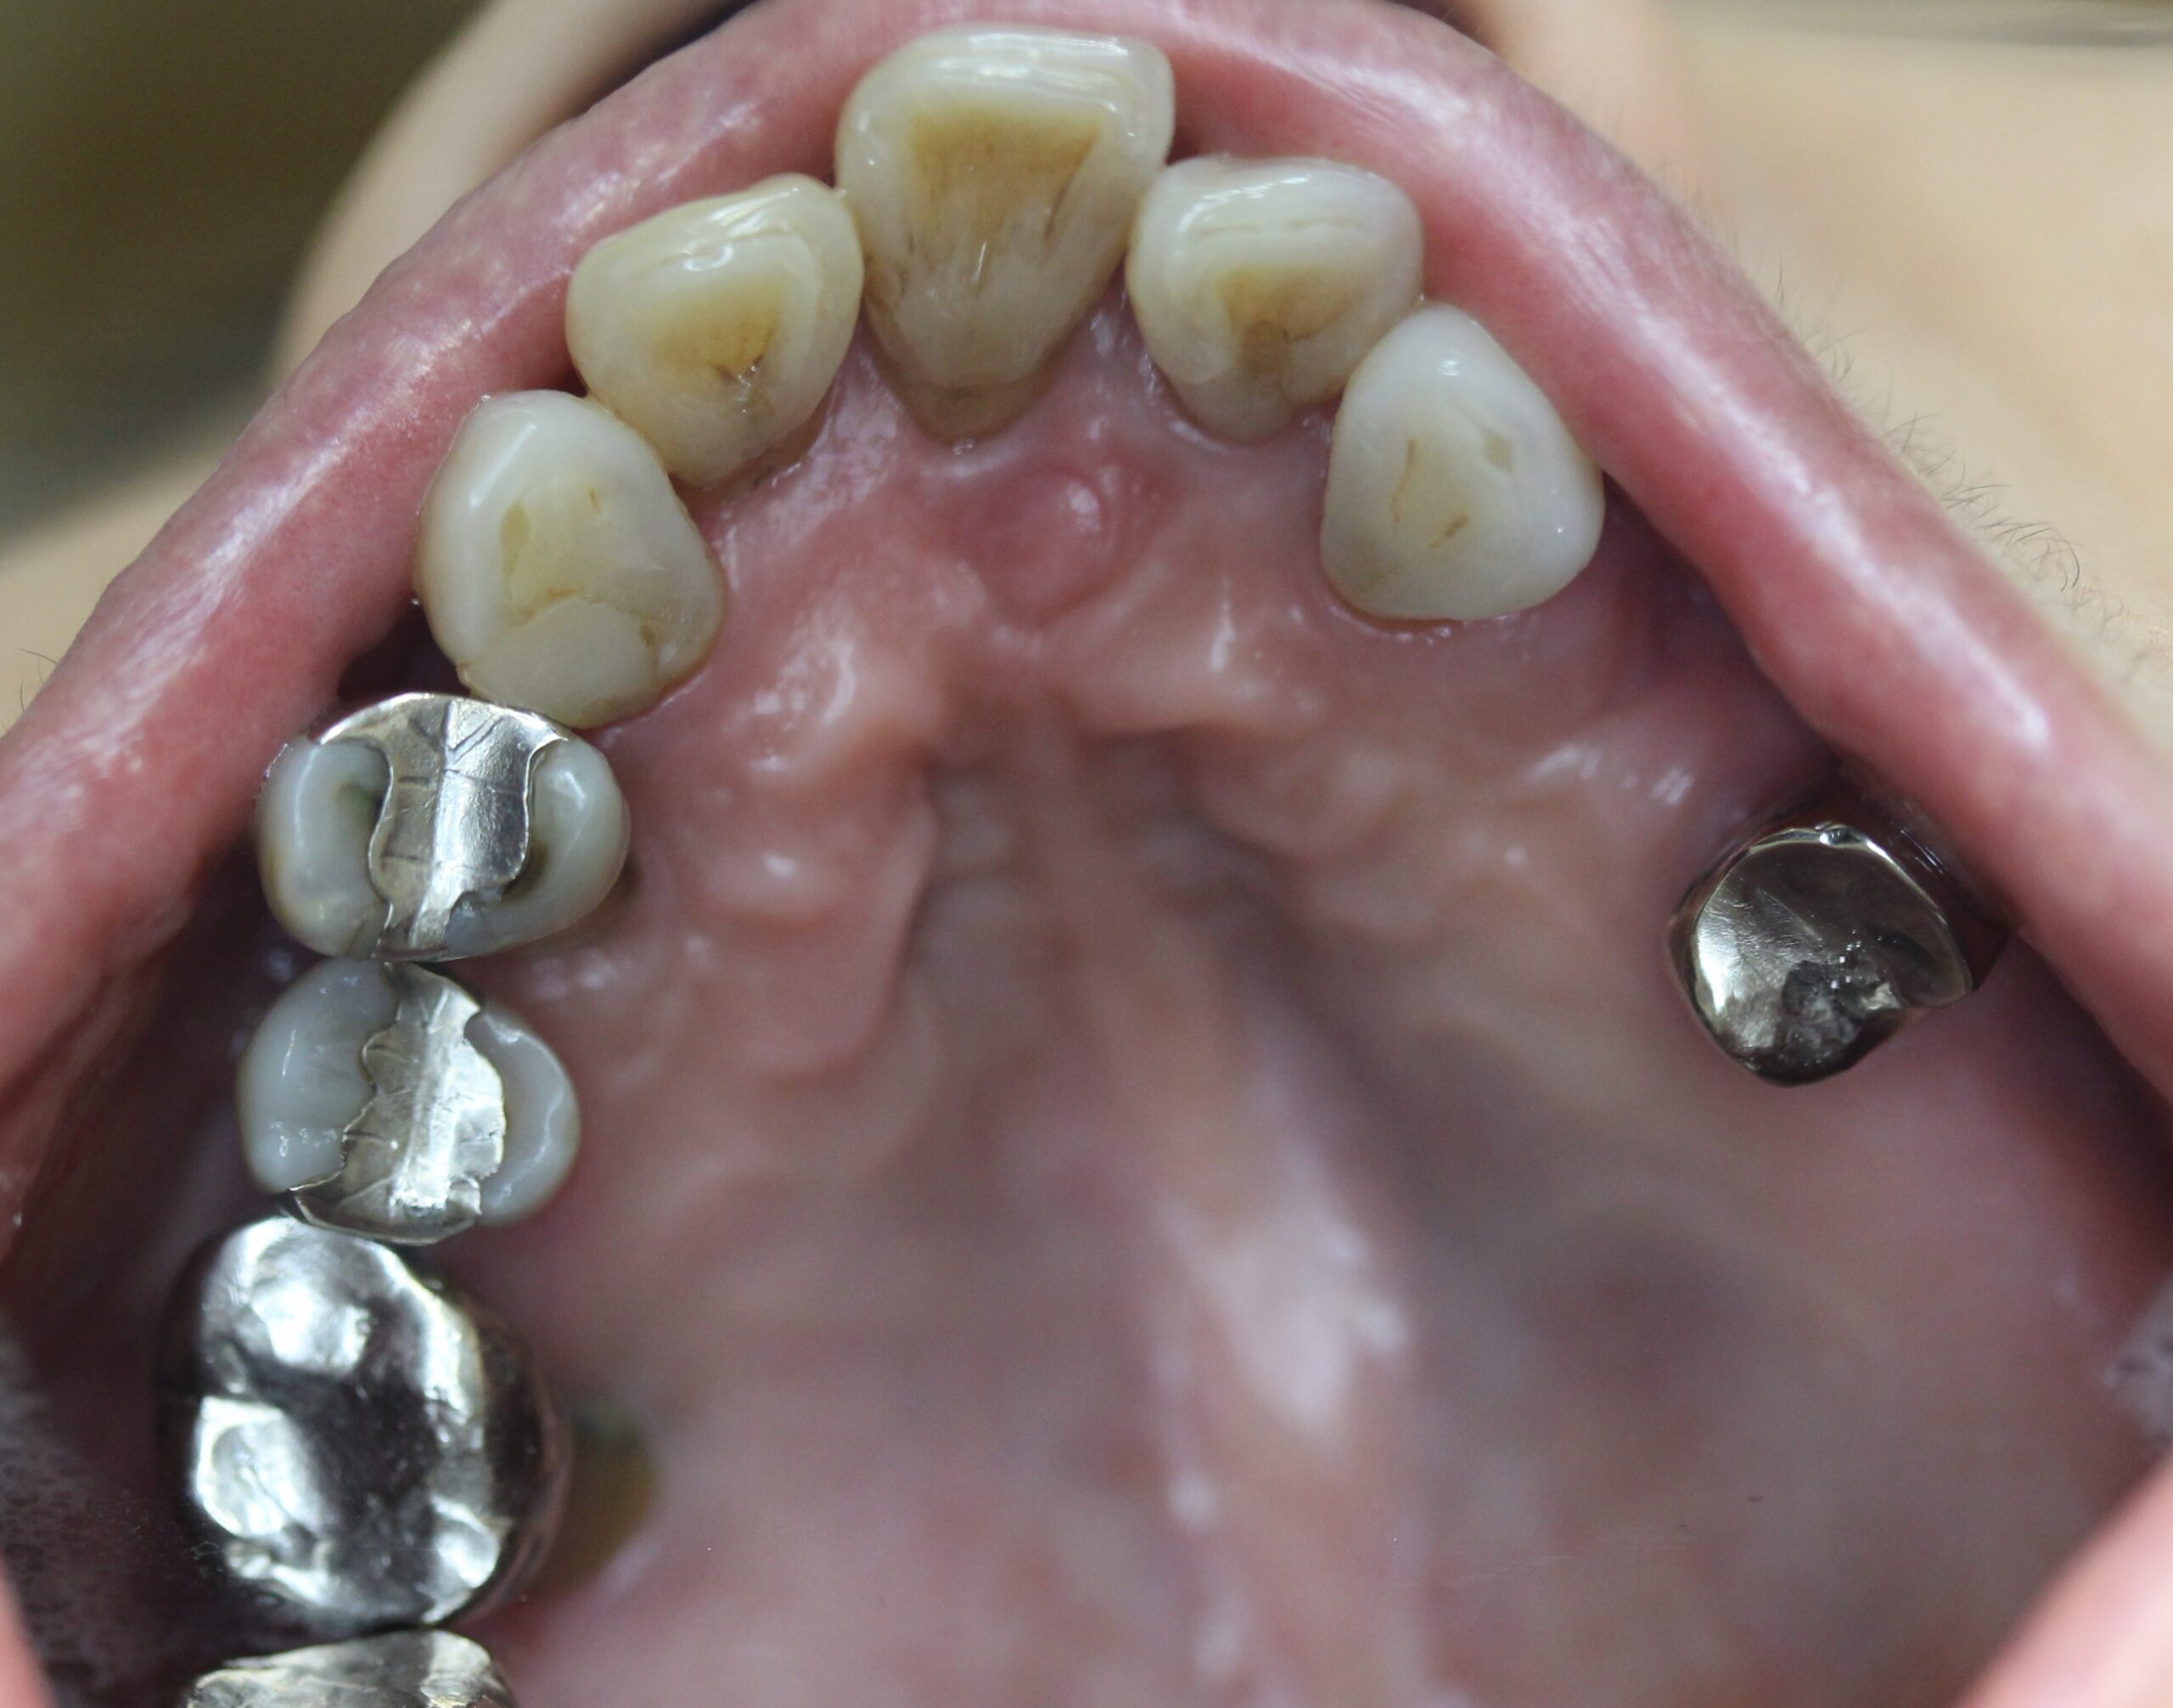

60代女性。歯がぐらついて噛めないので入れ歯を作り直したい。

入れ歯でちゃんと噛めないので新しく作り直したい。

上顎はコーヌステレスコープ、下顎はレジリエンツテレスコープにて治療を行なった。

【治療後】